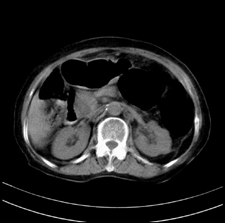

患者,女,75岁。腹痛,体黄5日,膝胸位时腹痛缓解。肝功能明日出来。彩超提示胆总管占位,未见血流信号。心电图提示s-t段改变。患者体质较弱,未能增强。

胆总管结石

胆总管多发结石

胆总管多发结石伴肝内外胆管轻度扩张。

胆总管上段,腔内有软组织密度影 ,ct值36-44hu。大家看有没有胆管癌的可能。

典型胆总管多发结石;增强扫描前后ct值是否发生改变是鉴别结石与占位的依据。